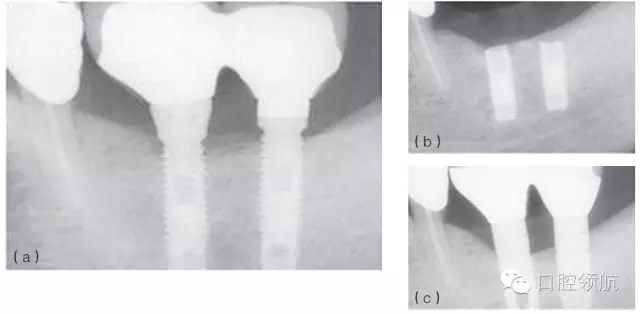

例如,在發(fā)生率低的種植體折斷病例中,感染和創(chuàng)傷經(jīng)常同時存在,或相繼發(fā)生。感染引起的種植體周骨喪失(種植體周圍炎)也可能導(dǎo)致種植體折斷。過載或創(chuàng)傷則是種植體折斷的第二個因素,種植體折斷的高度常常與骨-種植體的接觸水平相一致(圖6.4a~c)。也可相反,種植體周感染繼發(fā)于咬合創(chuàng)傷,導(dǎo)致種植體不能形成骨結(jié)合而失敗。(圖6.5a~c)

圖6.4 (a)18號、19號位點種植體出現(xiàn)邊緣骨吸收。(b)2年后出現(xiàn)折斷。(c)拔除了舊的種植體,新的種植體植入并進行修復(fù)。